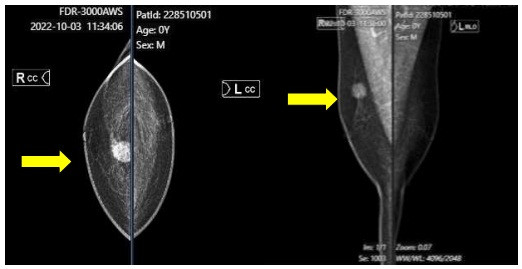

Quá trình thăm khám tình cờ phát hiện khối u vú phải, anh A. vào Trung tâm Y học hạt nhân và Ung bướu, để tiếp tục chẩn đoán và điều trị.

Sau khám lâm sàng và siêu âm, bệnh nhân đã được sinh thiết u vú phải ngày 4/10/2022. Các bác sĩ chẩn đoán xác định, anh A. có u tế bào hạt vú phải lành tính, kèm tăng huyết áp.

Bệnh nhân được hội chẩn chuyên khoa phẫu thuật lồng ngực và được chỉ định phẫu thuật cắt bỏ khối u vú phải. Sau phẫu thuật, vết thương liền tốt, không gặp các biến chứng hậu phẫu.